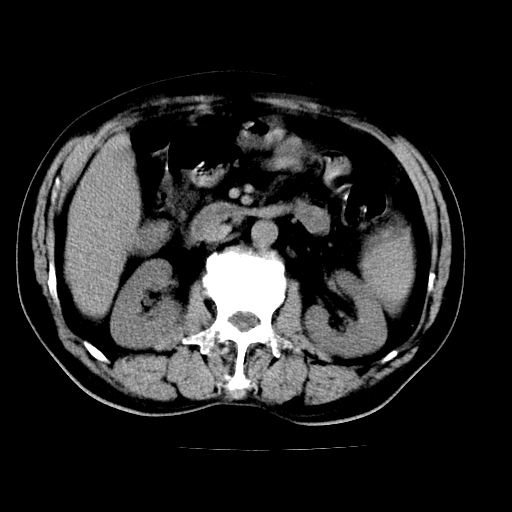

肝左叶占位性病变,并胆管扩张,符合胆管细胞癌ct表现,门脉左支受累,左肾囊肿。窗宽太窄了,其他的看不清

左叶胆管细胞癌累及胆总管,门脉左支受侵,慢性胆囊炎胆结石,左肾小囊肿

胆囊缩小,其内胆汁浓缩,也提示梗阻部位应该位于胆囊管起始部以上或是胆囊管受累及,支持肝外胆管癌。

支持 1肝左叶肝内胆管细胞癌伴胆总管及门脉左支受侵。2胆囊钙乳症。